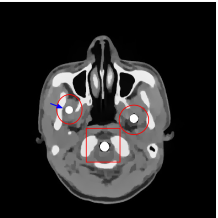

The proposed re-weighted JSR model requires a pre-estimation of the metal trace and weights in projection domain. They can be obtained fairly easily from a roughly reconstructed CT image using a simple reconstruction model. In this paper, we use the tight wavelet frame based analysis model [8]. This subsection describes the details on how metal trace and weights are computed using the NURBS-based cardiac-torso(NCAT) phantom [45]. Two metal components are implanted in the NCAT phantom as shown in Figure 1(a) and the simulated projection data is obtained from a multi-chromatic X-ray source. Details on the settings of the imaging system are postponed to Section 4.1.1.

The optimization problem (2.12) can be solved by the split Bregman algorithm [29, 8] efficiently, which is also equivalent to the alternating direction method of multipliers (ADMM) [24, 26, 28]. The reconstructed phantom image by model (2.12), denoted by , is shown in Figure 1(b). Metal location in image domain can be robustly estimated by the summation of the high frequency wavelet frame coefficients (Figure 1(c)) followed by a simple thresholding. Then, the index of the metal trace in Radon domain, denoted by , can be identified by the projection of the indicator function associated to the metal location (Figure 1(d)).

The NCAT phantom (shown in Figure 1(a)) and the cerebral phantom111http://see.xidian.edu.cn/vipsl/database_CTMR.html (shown in Figure 8(a)) are chosen as image phantoms. For the NCAT phantom, it has pixels. Two metal components (Titanium) are implanted in the image, which is shown in Figure 1(a) with red curves labeling the locations of the metals. For the cerebral phantom, it has pixels and three metal components (Titanium) are implanted. Both of the phantoms contain three major components, i.e. soft tissue, bone and metal components, and their linear attenuation coefficients can be found in [30].

Figure 7(a) shows that the reconstructed NCAT phantom from FBP has severe metal artifacts and is noisy. The reconstructed image from the unweighted JSR model (3.2) shown in Figure 7(b) has a better visual effect with noticeably less noise and metal artifacts. Sharp edges are also well preserved except for the blurry effects in the region surrounding the metals. The reconstructed image from NMAR shown in Figure 7(c) also has most of the metal artifacts suppressed and the regions surrounding the metals are much less blurry than the unweighted JSR. However, the unweighted JSR does a better job than NMAR in suppressing noise and preserving sharp image features away from the metals. TV-FADM is able to reconstruct images with minimum metal artifacts and noise, as shown in Figure 7(d). However, the metal components are fused with nearby structures which is highlighted by the red arrow. The reconstructed image from proposed re-weighted JSR model has the best overall quality with rather minor metal artifacts.

Figure 8 shows the reconstructed cerebral phantom from different methods. We highlight some regions with more distinct differences with red contours. Since the cerebral phantom contains more textures, it is more challenging than the NCAT phantom. The pros and cons of these methods are mostly the same as the previous example. However, we note that the reconstructed image from TV-FADM shown in Figure 8(e) has severe artifact, which is due to the well-known staircase artifact of TV regularization. We found that TV-FADM is relatively sensitive to the choice of its parameters. It is not easy to balance between sharpness of image features and metal artifacts reduction. The soft tissue around metal components is also not well preserved by the NMAR method as indicated by the blue arrow in Figure 8(d). Furthermore, the circled areas in Figure 8(d) show that there are still some artifacts around the metal. Same as the NCAT phantom, the proposed re-weighted JSR model has the best overall performance. Notice that the intensity of metals in Figure 8(d) and 8(f) seems lower than the rest of the reconstructed images. This is because we set the intensity of the metal components in the segmentation with the same mean value as that of bones. Increasing the value of metal components of can increase the intensity of metals in the reconstructed images, whereas it also introduces more artifacts around the metals.